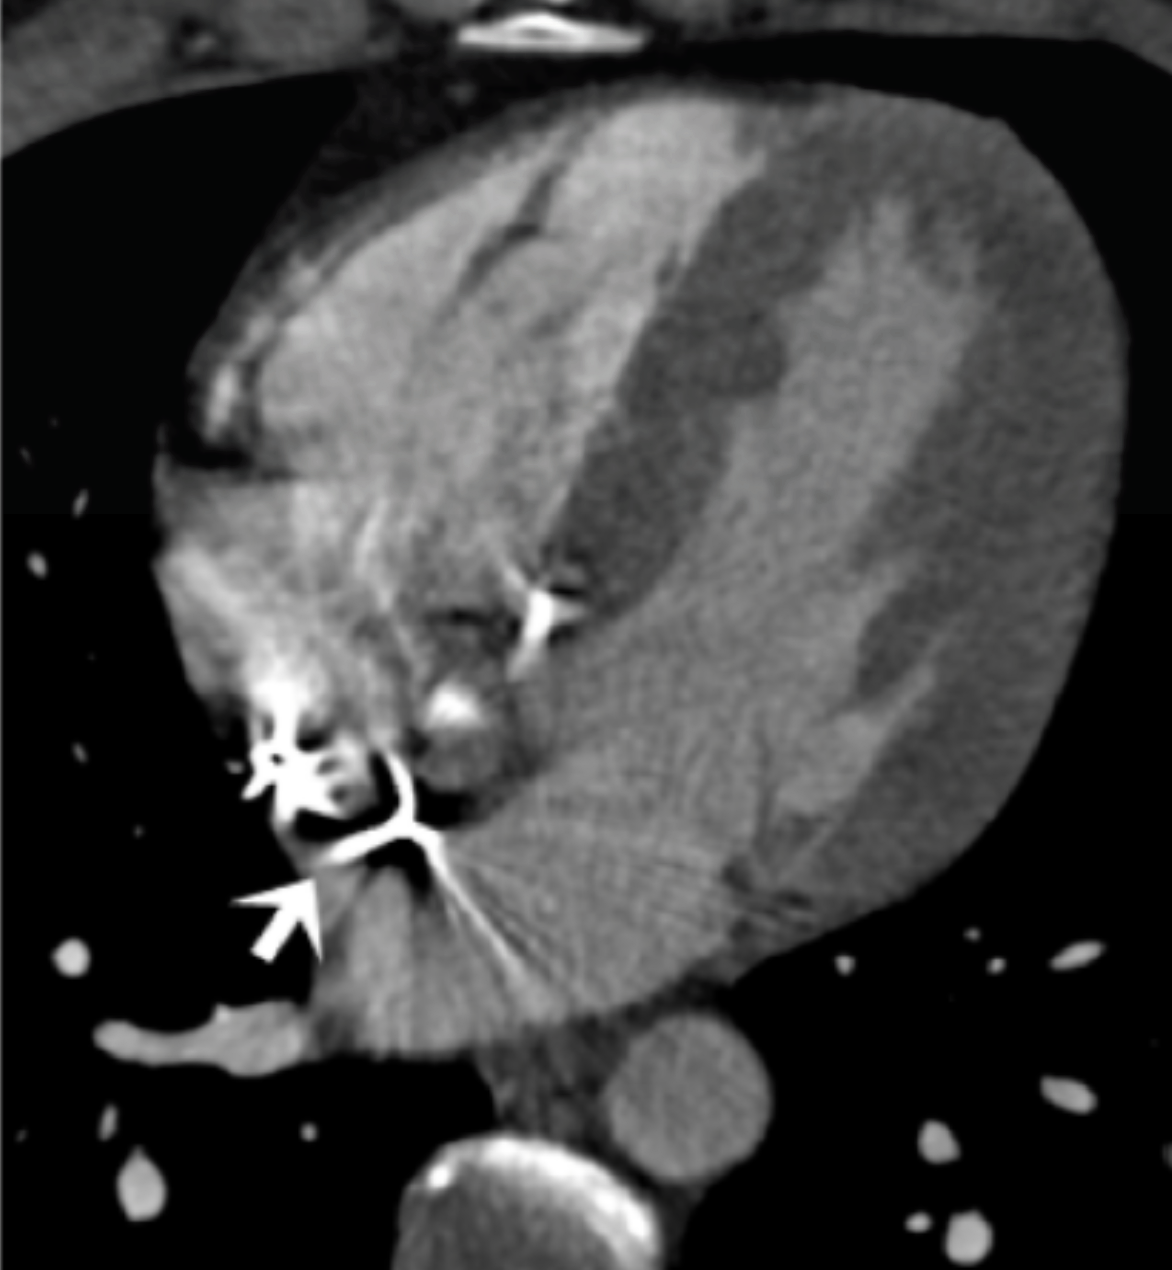

Describe the findings and diagnosis:

LV apical thrombus